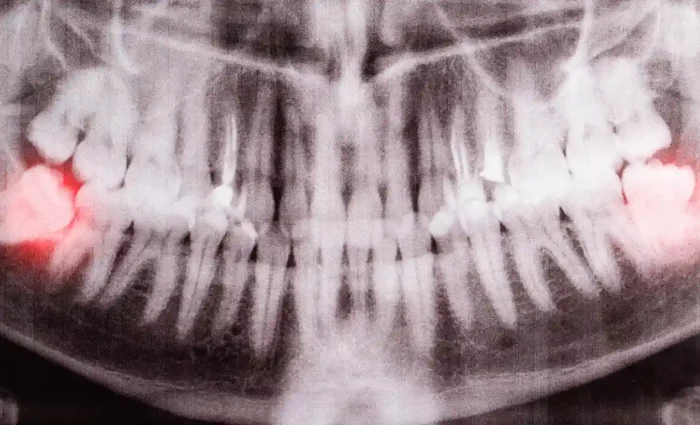

Medically Reviewed By Dr. Mert Albayrak, DDS Oral and Maxillofacial Surgeon Most dentists removed wisdom teeth as a preventive strategy for years. Early removal was thought to minimise congestion and infection. As dental science advances, specialists are questioning this standard practice. More specialists are arguing for a conservative approach, indicating that not everyone needs wisdom […]